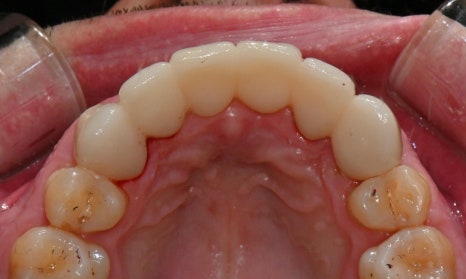

진단 결과, 교합시 하악 전치가 거의 보이지 않을 정도로 깊은 교합을 보이고 있었으며, 어린 시절 외상을 입었던 앞니는 치아 뿌리 부근에 광범위한 염증이 관찰되어 장기적인 유지가 어려운 상태였습니다. 이에 앞니 두 개는 발치를 결정하였고, 환자의 비교적 젊은 나이를 고려하여 가능한 한 최대한 치아를 보존하기 위해 앞니 부위 임플란트를 고려했습니다. 그러나 해당 부위 골 손실이 매우 심했고, 외국인 환자로 장기간 내원이 어려운 상황이었기 때문에, 광범위한 골이식을 동반한 임플란트 치료 보다는 비교적 짧은 기간 내에 기능과 심미를 회복할 수 있는 브릿지 보철 치료를 계획하였습니다.

또한 하악 전치가 혀 쪽으로 과도하게 쓰러져 있어 보철적으로 위치를 회복하기에는 한계가 있어, 발치 후 후 상하악 모두 브릿지 보철로 치료 계획을 수립하였습니다. 하악 전치를 원래 자리에 위치시킬 경우 뼈가 너무 올라와 있었기 때문에, 발치 후 아래 앞니 부위 골성형도 시행하기로 하였습니다.

진단 모형을 바탕으로 1차 디자인 상담을 진행하였습니다. 그 후 브릿지 보철을 위해 많이 삭제해야 하는(깎아야 하는) 치아에는 신경치료를 하고, 일차적인 임시 보철물을 만들어드렸습니다. 이렇게 만든 임시 치아를 실제 입에 넣어보며 다시 한번 상담을 진행하는데요. 모형에서 볼 때와 입안에 착용했을 때 느낌이 조금 다를 수 있기 때문입니다. 이 과정에서 환자의 얼굴이나 미소와 조화로운지, 발음이나 교합 시 불편함은 없는지 꼼꼼하게 확인하는 것이 필수적입니다. 이 환자분은 외국인이셨지만 치료에 매우 적극적이셨으며, 다행히 임시 치아를 오래 사용해볼 수 있었습니다. 1~2주간 직접 사용하며 관찰한 후, 디자인에 대한 최종 상담을 진행하고 최종 보철물을 제작하였습니다.

보철물의 단점 중 하나는 시간이 지나면서 잇몸이 내려가면, 인공치 아래에 공간이 생겨 음식물이 끼기 쉽다는 점입니다. 하지만 발치 후 즉시 보철을 진행하면, 인공치를 발치한 자리에 맞게 제작할 수가 있어서 추후 잇몸이 내려가더라도 인공치가 마치 자연치처럼 잇몸 안 깊숙이 자리하게 됩니다. 이 환자분의 경우에도 발치 직후 바로 수복하는 이점을 활용하여, 인공치를 모두 깊게 위치하게 제작해 문제를 최소화 하였습니다.